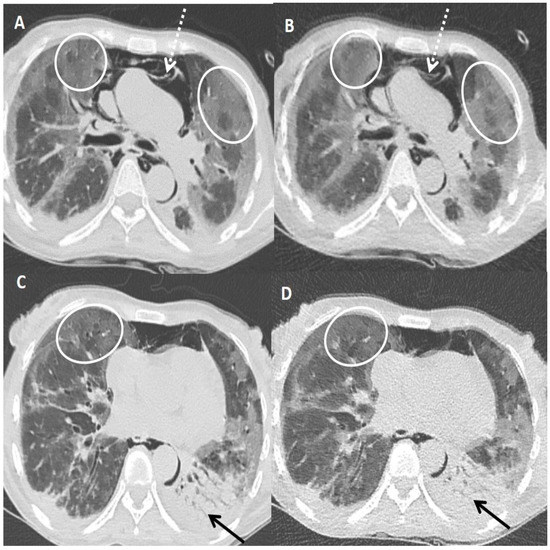

Figure 3.

A 45-years old female patient tested positive for COVID-19. Standard dose CT (SDCT) chest (A,C) and corresponding ultra-low dose CT (ULDCT) chest (B,D) showing areas of GGOs (white circles) and patchy consolidation with air bronchogram (black arrows). Pneumomediastinum was also seen (dotted white arrows). The effective radiation dose for SDCT and ULDCT was 4.13 mSv and 0.25 mSv, respectively, while the CT severity score calculated on both SDCT and ULDCT was similar (19/25).